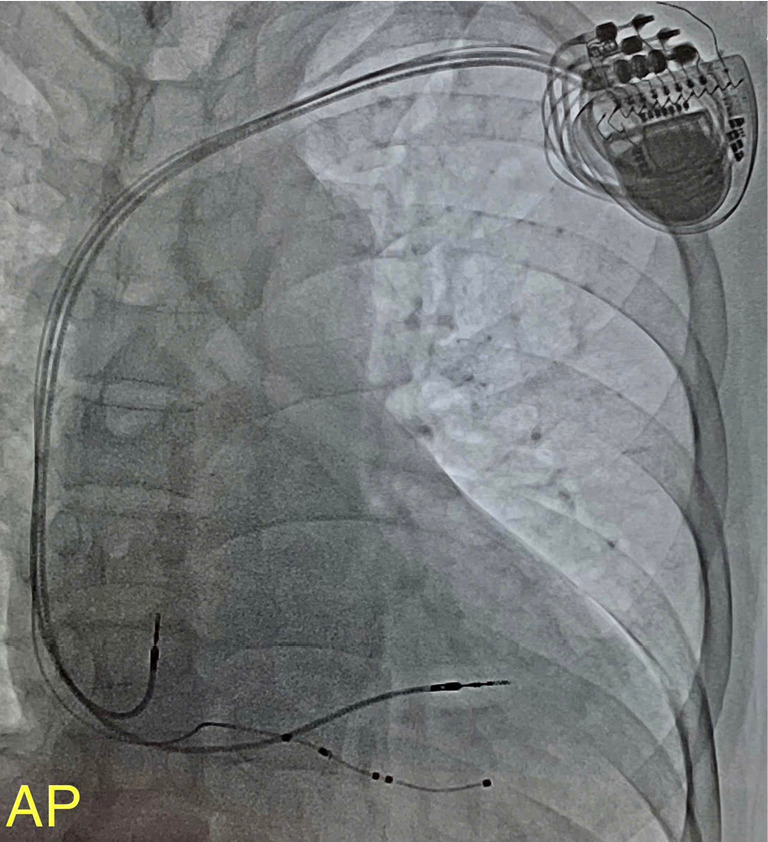

背景:多项研究表明,心脏再同步化治疗(CRT)能有效改善心力衰竭的预后。CRT已被证明可以改善患者的生活质量,降低患者再入院和死亡的风险。然而,显著比例的接受CRT的个体没有反应。因此,我们进行了这项研究来描述CRT的特征,并报告了在越南出院1年后的结果,以及对CRT无反应的预测因素。方法:这是一项多中心、双视角队列研究,纳入了胡志明市五家医院的所有CRT植入患者:胡志明市大学医学中心、胡志明市心脏研究所、Tam Duc心脏医院、通芽医院和Vinmec中央公园医院。所有患者均按照既定指南接受治疗,出院后随访1年。主要结局包括出院后1年的再住院率和死亡率。次要结果包括与手术相关的早期和晚期并发症。结果:2016年4月至2020年4月,共纳入5家医院CRT植入成功病例88例。男性居多(68.2%),平均年龄62.5±13.4岁,入院时为纽约心脏协会(NYHA) III/IV级(98.9%),平均左室射血分数(LVEF)为24%±5.9%。早期并发症发生率为9.1%。总死亡率为12.5%,其中6.8%发生在1年随访期内。患者出院后1年内再入院率显著降低(P=0.001)。此外,NYHA功能也有显著改善。结论:正确使用CRT设备可改善心衰症状、死亡率和再入院率。有几个预测心脏再同步化治疗失败的因素。这些信息有助于我们了解受限制的患者群体并开发更好的治疗方法,特别是在低收入国家。

Results: Between April 2016 and April 2020, 88 cases of successful CRT implantation from five hospitals were enrolled. The majority of the population was male (68.2%), mean age was 62.5±13.4 years old, New York Heart Association (NYHA) III/IV at admission (98.9%), and the mean left ventricular ejection fraction (LVEF) was 24%±5.9%. The incidence of early complications was 9.1%. The overall mortality rate was 12.5%, with 6.8% occurring within the 1-year follow-up period. The population experienced a significant decrease in readmission rate within 1 year after discharge (P=0.001). Additionally, there was a notable improvement in the NYHA function (P<0.001) and an enhancement in the quality of life (P=0.001). Five characteristics correlated with the lack of response to CRT were history of dobutamine usage, QRS interval (QRS) length before implantation, severe ventricular arrhythmias before implantation, atrial fibrillation after implantation, and severe ventricular arrhythmias after implantation.